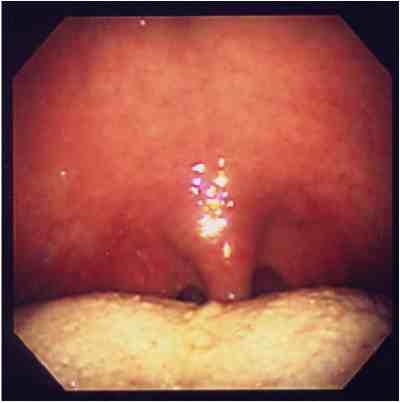

無呼吸の原因と考えられる扁桃肥大によるのどの狭窄に対し,扁桃摘出術を行い,

軟口蓋低位と口蓋垂の伸長に対し,UPP(uvulopalatoplasty)を行った例。

手術前手術後

のどの奥が広くなっているのがわかります。